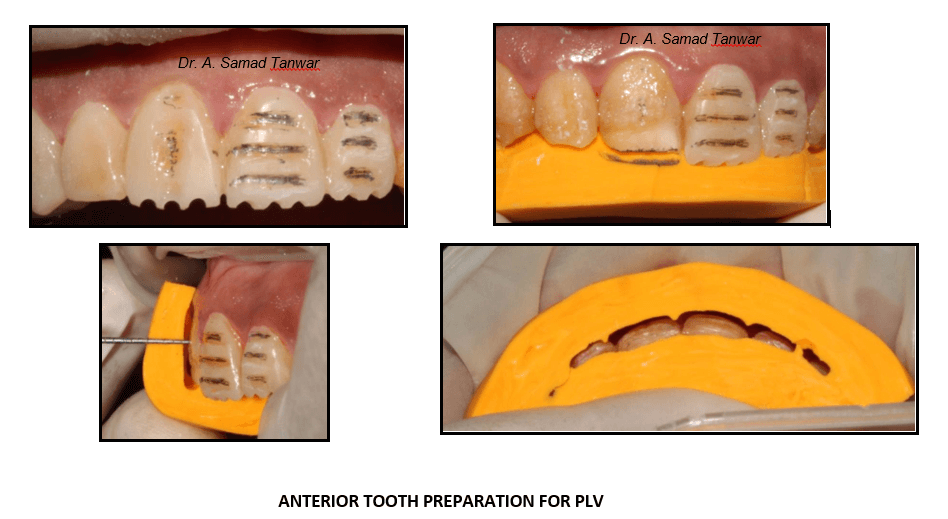

The preparation should be conservative which is the main principle governing the fabrication of ceramic

We start with the tooth preparation using the mock-up in place. Horizontal depth grooves were made using depth

The thickness of the ceramic laminate should be 3-0.5mm

A chamfer finish line is given and a bevel is given at the incisal edge to give a butt joint.

The preparation can be checked using